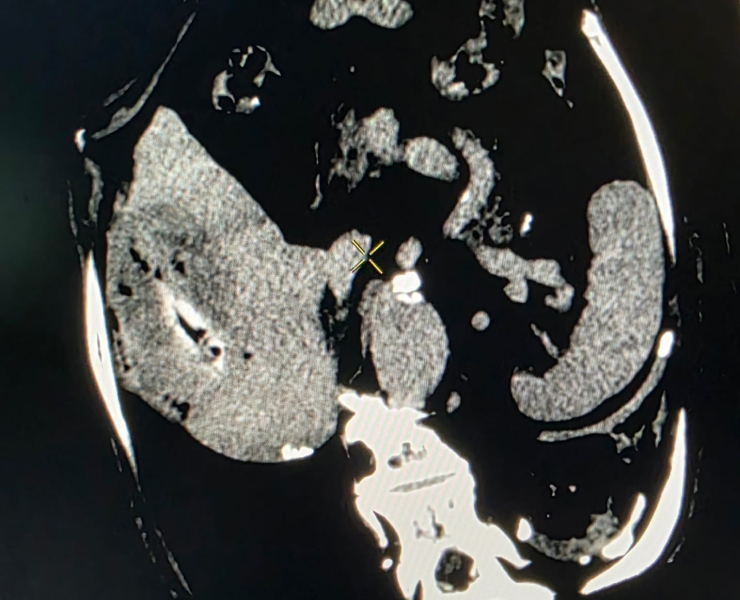

Insertion of microwave needle treatment of cancer

- Thermal ablation (radiofrequency or microwave): destroys tumour tissue by heating it from within through a thin needle placed under USG/CT guidance.

Microwave ablation of liver cancers

Kidney cancer treatment by Microwave Ablation method

Post treatment